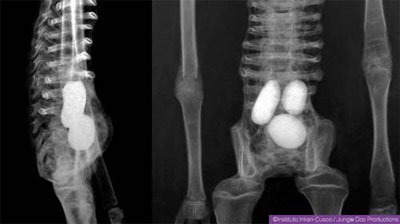

La créature est dotée d’un appareil reproductif complet, dans lequel se trouveraient…des œufs ! Notamment un 4ème œuf encore en formation. Comment fabriquer artificiellement un tel dispositif reproductif, aussi petit, dans le seul but de supercherie ? Celui qui aurait créé de telles contrefaçons serait un génie. Ce système « obivipare » n’a pas d’équivalent chez aucun animal connu. Certains émettent l’hypothèse d’un être hermaphrodite autonome.

Autre point : Josefina présente au niveau du crâne une spécificité que l’on ne retrouve chez aucune espèce terrienne connue : le foramen magnum, un trou à la base du crâne, est carré chez elle. Les ensembles vasculaires et nerveux se trouvent à l’arrière de la colonne vertébrale, alors que chez nous c’est l’inverse.